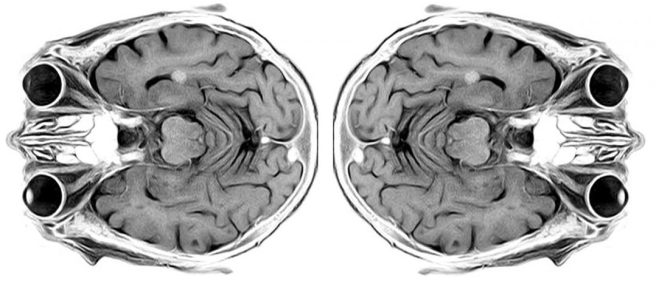

- Analysing the largest imaging cohort in Parkinson’s to date (n=3,096), researchers report widespread cortical & subcortical atrophy in PD is associated with advancing disease stage, longer time since diagnosis, & poorer global cognition (Click here to read more about this).